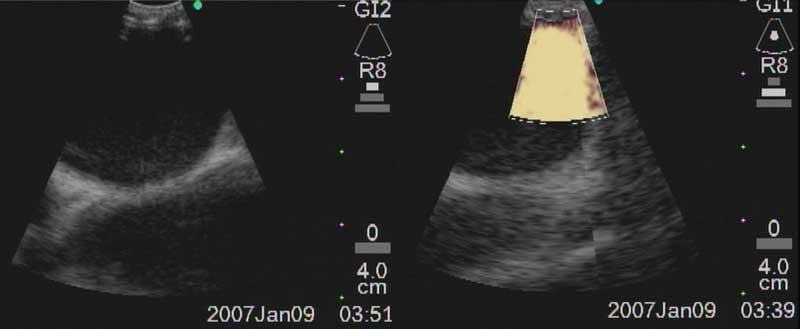

Figure 6a: Ultrasound image of R main pulmonary artery with (right) and without (left) color Doppler.

Figure 6b: Biopsy of right paratracheal node (arrow) with superior vena cava visualized in its long axis anteriorly.